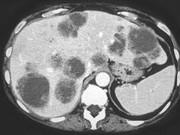

问题 男,54岁,患者1年前行结肠癌手术,癌胚抗原增高,影像检查如图,最可能的诊断是()

选项 A.多发结节性肝癌 B.结肠癌肝转移 C.多发性肝脓肿 D.多发性肝囊肿 E.肝淋巴瘤

答案 B